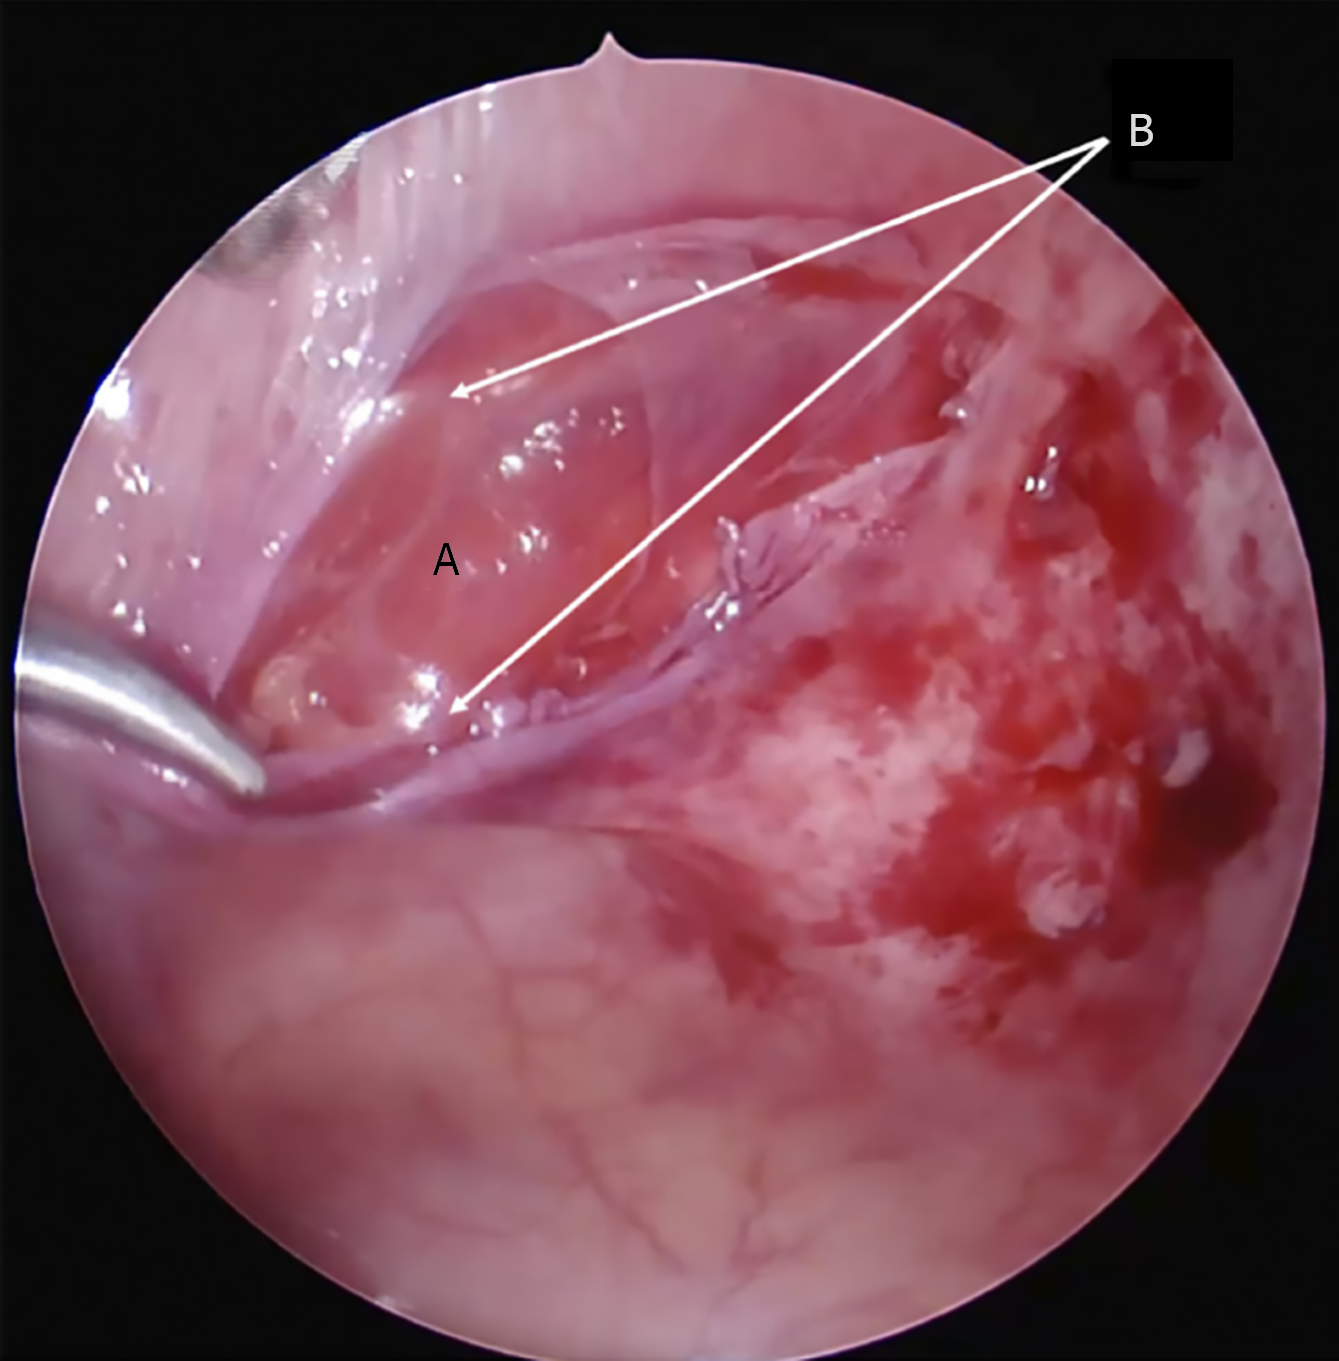

Figure 6 Laparoscopic view of Spigelian hernia.

A: Internal oblique muscle; B: Edges of the transverse fascia defect.